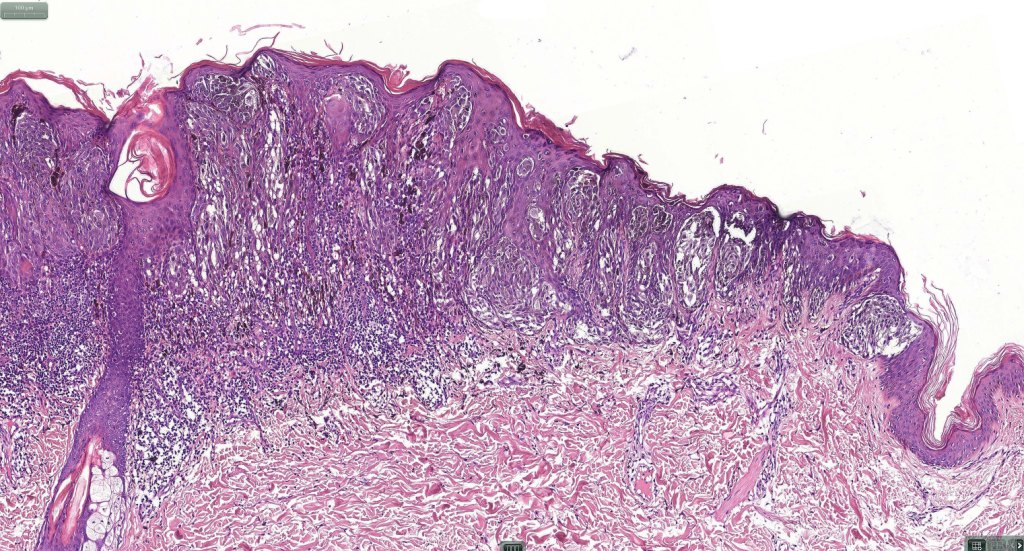

•Sharply circumscribed (begins and ends with a nest), symmetrical dome-shaped lesion. Symmetry is both horizontal and vertical (see image below)

•Wedge-shaped with the base uppermost or sometimes plaque-shaped silhouette

•Hyperkeratosis & acanthosis, sometimes very marked

•Superficial vascular ectasia very frequently present

•Junctional nests often vertically orientated, dyscohesive with a surrounding retraction artifact

•Lymphocytic infiltration at the base of the lesion